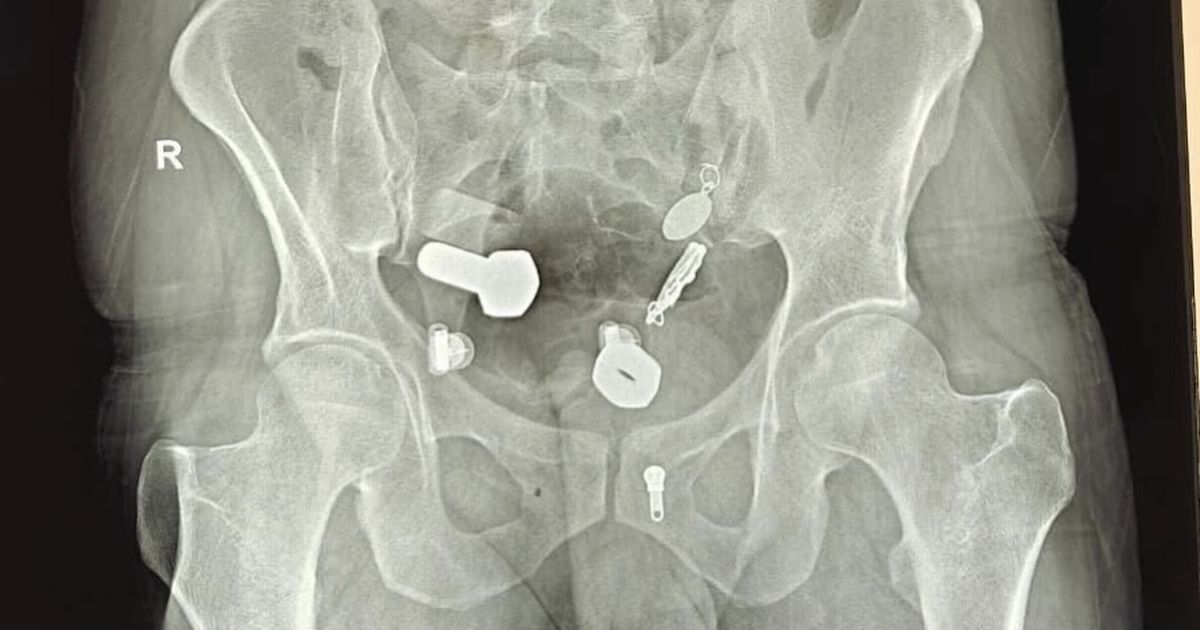

حاول الأطباء في البداية إزالة المجموعة الغريبة من الأجسام المعدنية باستخدام التنظير الداخلي، لكنهم اضطروا إلى إجراء عملية جراحية استغرقت ثلاث ساعات لإخراج كل شيء